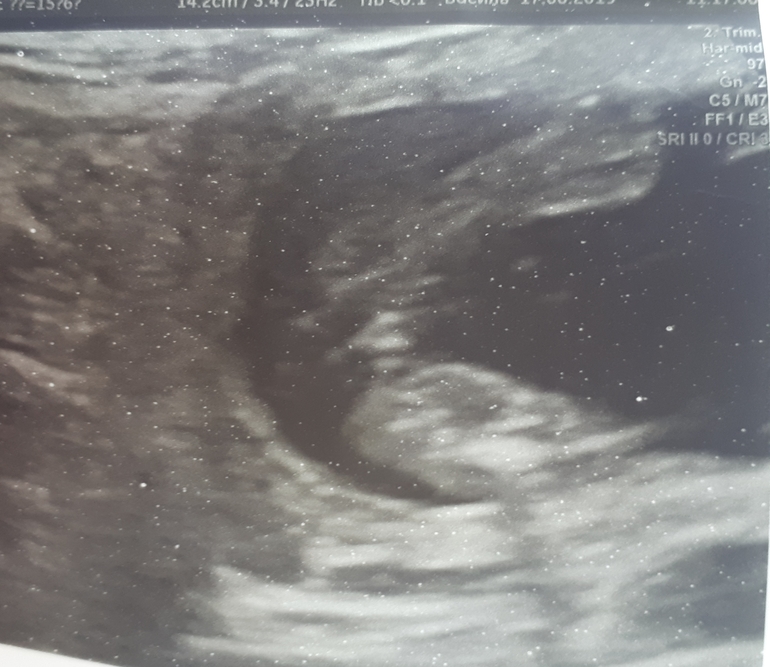

Дополнила!!!Девчули кто разбирается?Узи в 16 нед...

Хочется сказать девочка, но не четкое фото, может и мальчиком быть малыш.

Ну наверное точнее к 19-21неделям узнаете. Мнения расходятся)

Мне кажется пацан, врач то что заказал?) не томите))

Так а врач что сказал? Хотела сказать девочка...но что то и на яички похоже. У нас как бы более плоско было...просто 2 полосочки

Мне на мальчика похоже, у девочки там чётко видно раздвоение, а здесь, как яички и даже, возможно, виднеется маленький писюн. Тут давеча была история, где девочка в мальчика превратилась, так там ещё явней была якобы девочка, во всяком случае очень похоже на ваше фото, а оказался через несколько недель явным мальчиком. Поищите здесь, если не лень, не так давно было.